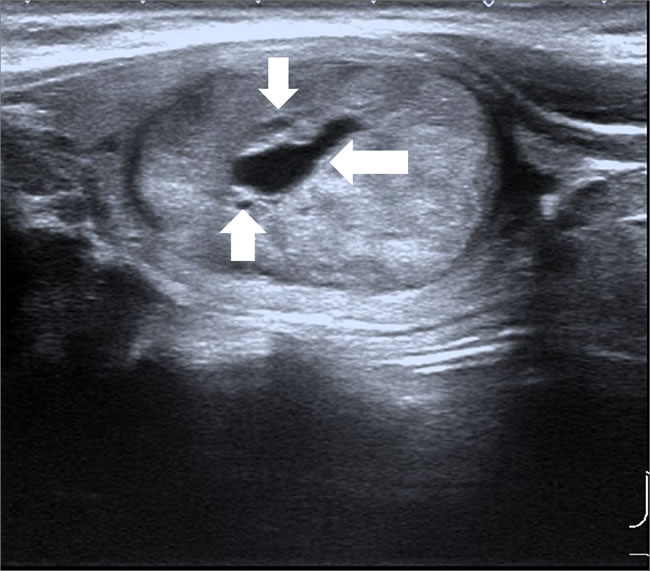

Figure 1: Male patient, 33 years old, MEN 2 MTC. Lesion was oval in shape, with well-defined margin, mixed echogenicity, some cystic changes (arrows).

Specific ultrasound characteristics of 44 MTCs and 119 PTCs are shown in Table 3. Like PTC, MTC showed ultrasonographic features of malignant nodules, including marked hypoechogenicity (37/44, 84.1%), ill-defined margin (28/44, 63.6%), microcalcifications (24/44, 54.5%), and abnormal cervical lymph node (16/35, 45.7%). However, compared with PTC, MTC had significantly larger lesion size (2.10 ± 1.70 cm vs. 0.80 ± 0.70 cm, P < 0.001). Most of the lesions in MTC were oval shaped (Figure 1). The MTC group only had three lesions (3/44, 6.8%) with aspect ratio > 1, which was significantly less than the PTC group (68/119, 57.1%, P < 0.001) (Figure 2). The MTC group had seven lesions (7/44, 15.9%) with a mixed echogenicity (Figures 1 and 3); this was significantly higher than the PTC group (3/119, 2.5%, P = 0.003). The MTC group had 40 lesions with enhanced blood flow signals (40/44, 90.9%) (Figure 4), which was significantly higher than the PTC group (47/119, 39.5%, P < 0.001). Both MTC and PTC groups showed abnormal cervical lymph nodes; the MTC group had 16 cases (16/35, 45.7%) and the PTC group had 32 cases (32/96, 33.3%). The difference between the two groups was not statistically significant (P = 0.21).